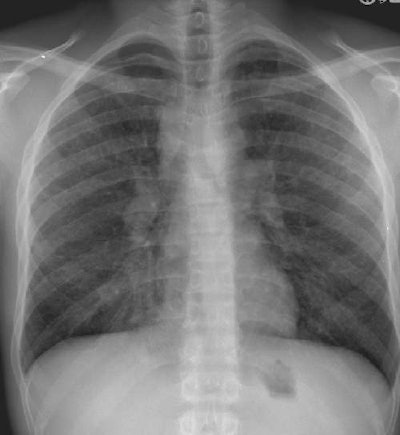

Sarcoidosis Stage II

The CXR demonstrates the presence of right paratracheal and hilar adenopathy. Coupled with this finding is the presence of interstitial lung disease which appears as a coarse reticulo-nodular pattern.